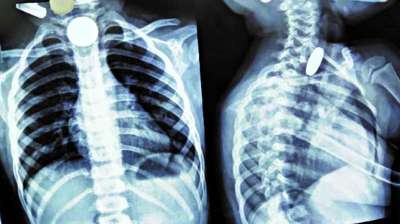

खिलौना नहीं सिक्का था! बच्चे ने निगले 5-10 रुपये के सिक्के, डॉक्टरों ने ऑपरेशन कर निकाले

24 Jul, 2025 04:09 PM IST | R18NEWS.IN

दिल्ली : दिल्ली के एक सरकारी अस्पताल के डॉक्टरों ने 12 वर्षीय बच्चे की जान बचाई है। बच्चे ने पांच और दस रुपये के तीन सिक्के निगल लिए थे। सिक्के...